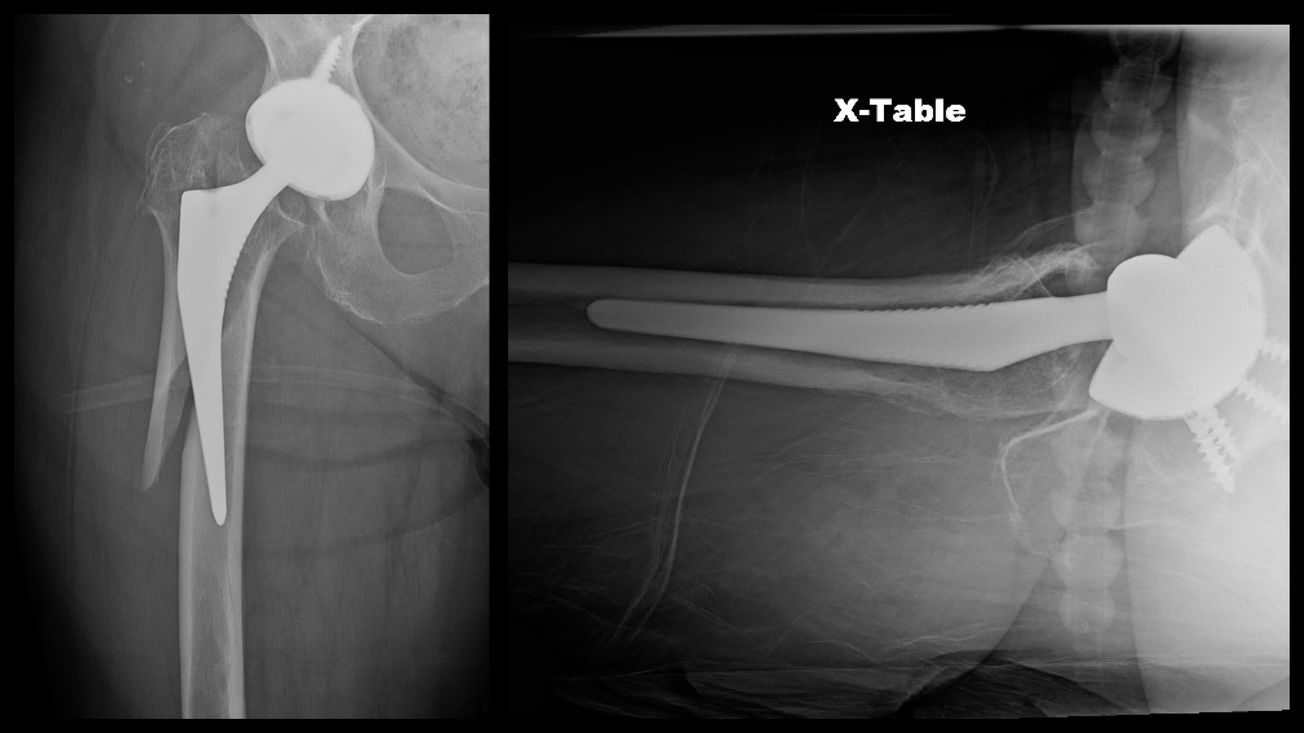

Periprosthetic Femur Fracture ORIF, Stem Revision

Adam Sassoon

May 8, 2022